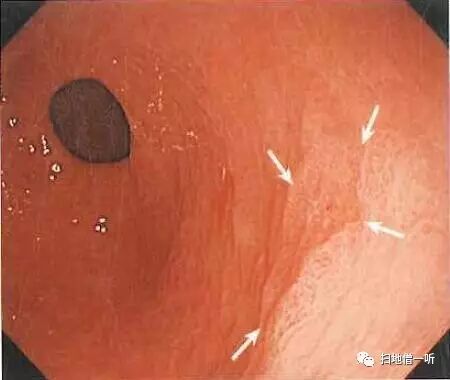

A:第二个病变胃癌在图1及图2。(此次检查被漏诊)

回顾性观察图1可见胃窦部后壁小片状发红粘膜,胃窦蠕动时观察不佳。图2可见凹陷型病变,鉴于没有通过抽气吸气等详细观察,故此次漏诊。

半年后再次行内镜检查所见:胃窦后壁凹陷性病变明显,周围伴反应性隆起。